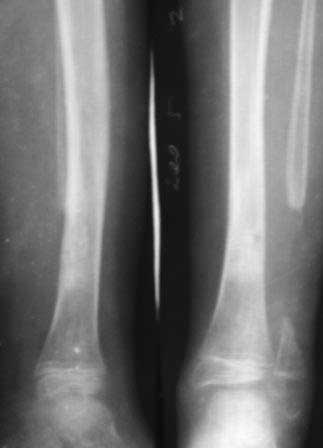

Девочка 2005г.р. В середине 2008 г падает с велосипеда с дедом, возможно был перелом н/з костей левой голени, лечение у знахаря-табиба, но ребенок не смог бегать, часто падал, начал хромать. Май 2009г. обратились к нам, установлен д-з « вялоконсолидирующаяся перелом н/з б/берцовой кости, несросшийся перелом м/берцовой кости со смещением по ширине». Мы решили гипсовая повязка и ходьба с нагрузкой, но по категорическому требованию родителей исправить деформацию м/берцовой кости, произвели операцию ( на свою голову )»о/ репозиция и и/м фиксация спицами м/берцовой кости». Теперь началась самая интересная история! Ч-з недели две в обл. п/о раны м/берцовой открылась свищ с кровянистым выделением, гноя не было, на р-грамме лизис концов отломков м/берцовой кости, к-рый начал прогрессировать, консультирована онкологами, цитология, с подозрением направлена в центральные институты, сделана КТ, онкологическое исключили, в августе попали в остеомиелитический центр, где произведена резекция м/б на протяжение 6-7см, все зажило и выписали (снимок-1). 2010г в мае повторно получила травму, наложена гипсовая повязка (снимок-2) и через 1-2 месяца в одном из центральном институте произведена КДО аппаратом Илизарова , который снят ч-з три месяца (снимок-3) и долго ходила на костылях-мать заставила, как начала наступать, появилась деформация, заказали ортез и так ходила, но деформация прогрессировала, Обратилась к нам в апреле 2012г,(снимок-4) произведена постепенная коррекция на аппарате, и замена на БИОС 01.03.12г плечевым гвоздем, ЭОП нет, поэтому осталась несколько антекурвация (снимок-5), ребенок ч-з неделю начала ходить.Повторный осмотр 22.06.12г- деформация усиливается, за три месяца сращение очень слабое.(снимок-6). (Жаль что многие р-снимки не сохранились, мать обещала хотя бы часть найти)!Что теперь делать?